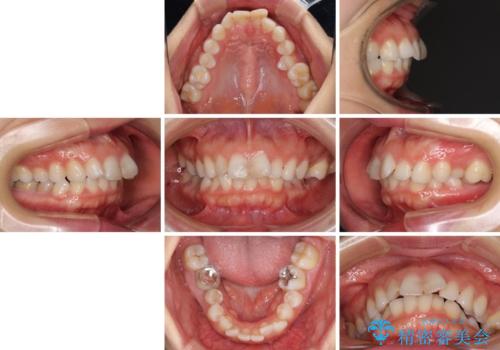

出っ歯と咬み合わせを改善 ワイヤー装置の抜歯矯正

- 口元の閉じにくさと、奥歯の咬み合わせを気にして来院された患者様です。

左下の大臼歯2本が顕著に舌側に傾斜しているため、まずは奥歯の咬み合わせを改善をし、その後上下左右の第1小臼歯4本を抜歯することで口元を引っ込めながら整えることとしました。

奥歯の咬み合わせ改善には1年ほどの期間と処置中の噛みにくさを強いることとなりましたが、抜歯後はスムーズに治療を完了させることができました。

歯ぎしりの際に奥歯が干渉していた咬み合わせも理想的な状態に改善できました。